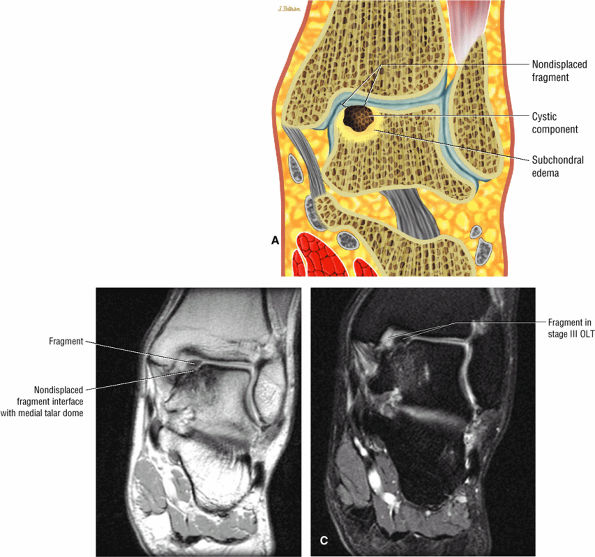

Stage IIB: Incomplete separation of the fragment (Fig. 5.97)

FIGURE 5.97 ● Stage II (IIB) OLT with a shallow and wafer-shaped fragment and incomplete separation from the lateral talar dome. (A) Coronal T1-weighted image. (B) Coronal FS PD FSE image. (C) Sagittal FS PD FSE image. (D) A nondisplaced partial fracture shown in a color graphic corresponding to either a communication with the talar dome or an open articular surface lesion with incomplete separation of the fragment. Subchondral cystic lesions are associated with extension of a fracture to the talar chondral surface.